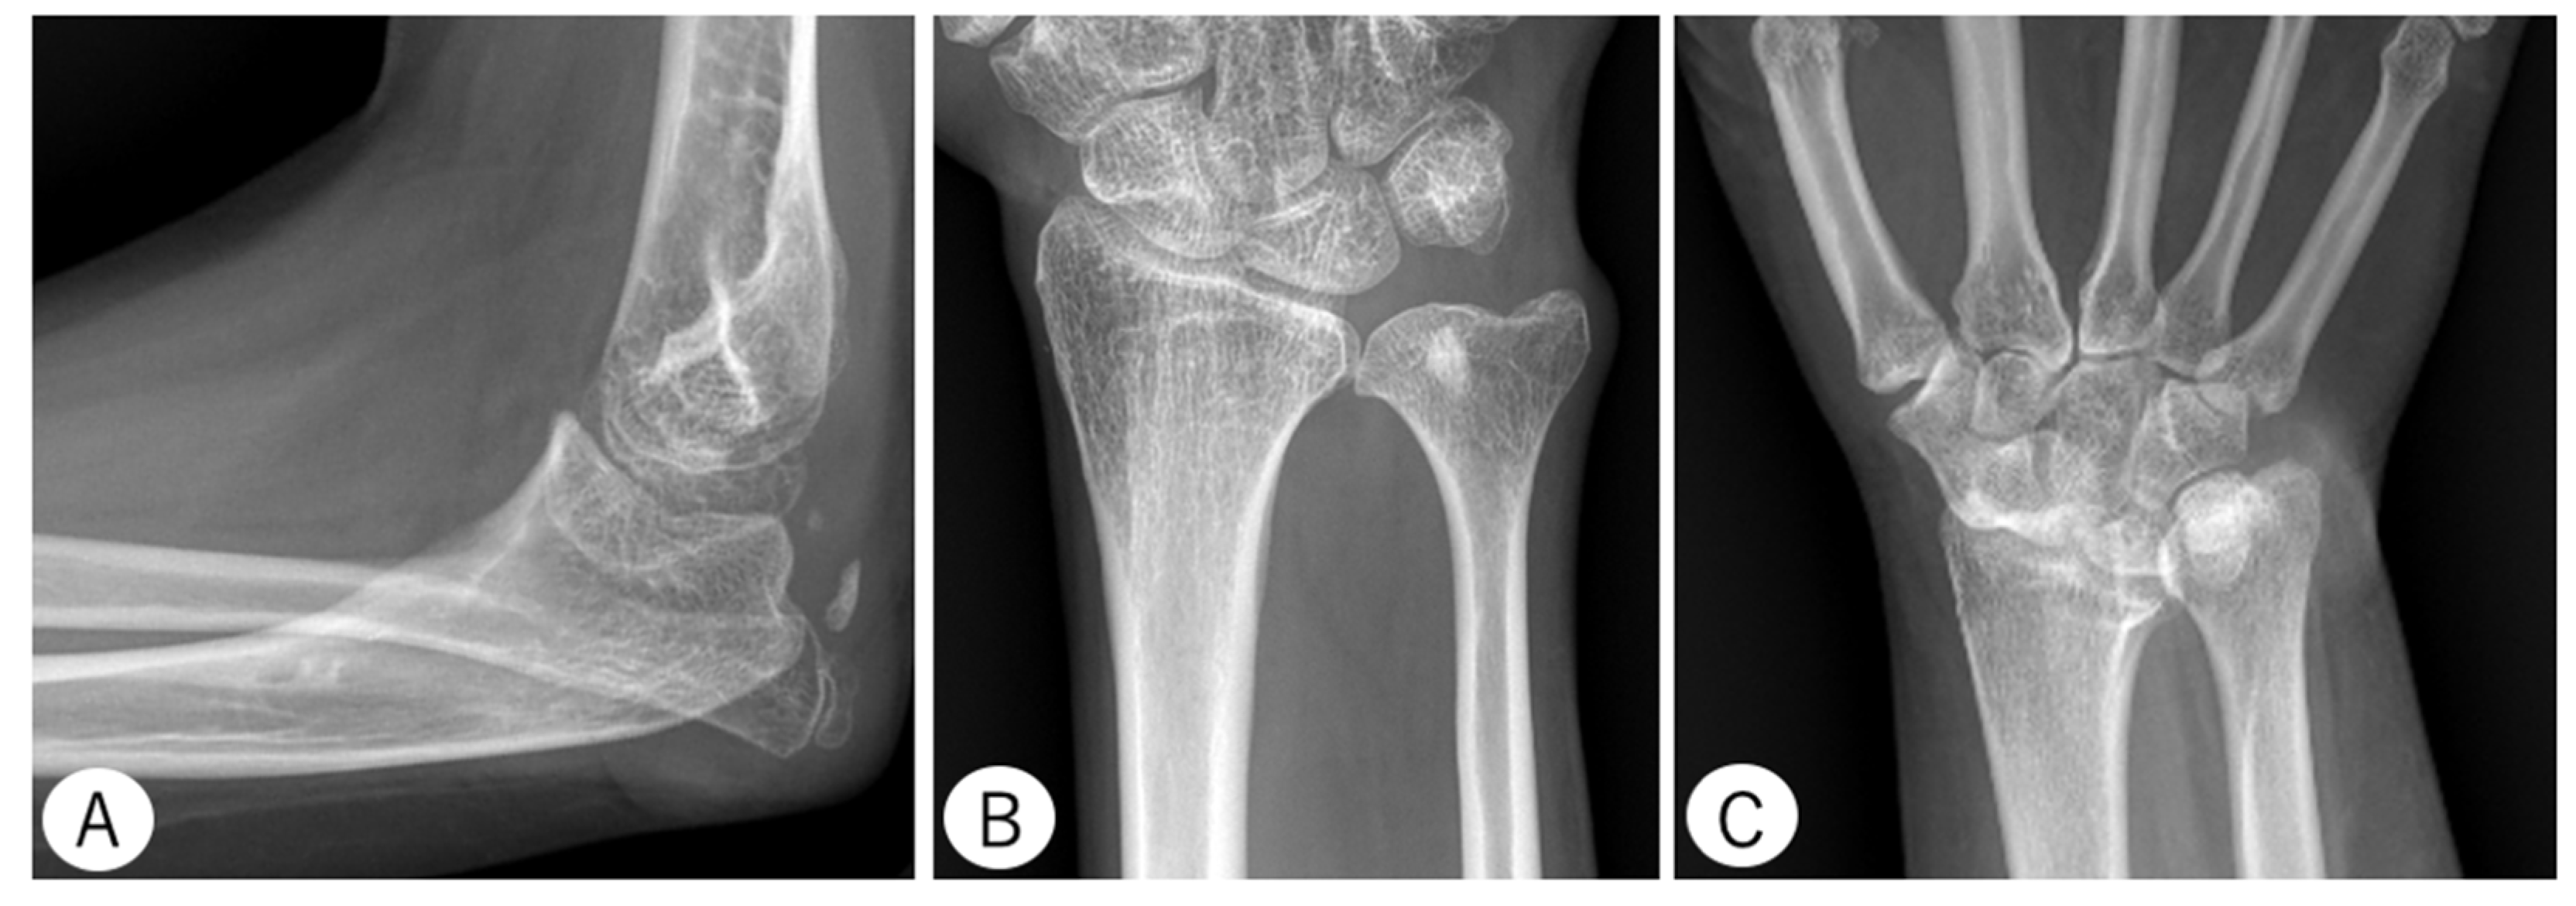

Six patients (46.2%) sustained a radial head dislocation (four adults, two children). In addition, 5 patients (38.5%) exhibited ulnar head deformity (five adults), and two patients (15.4%) had unilateral fusion of the scaphoid and the trapezium (two adults) (Figure 4). Four patients (30.8%) had elbow OA, and three patients (23.1%) had distal radioulnar joint (DRUJ) OA. OA was only observed in adult patients, and hand OA was not observed.

Figure 4.

Radiographs of example cases. Patient 3 at age 11 years shows an angularly deformed proximal ulna and posteriorly dislocated radial head (A). Patient 12 at age 39 years shows a narrow ulnar diaphysis and an enlarged distal area (B). Patient 11 at age 31 years shows a fused scaphoid and trapezium (C).